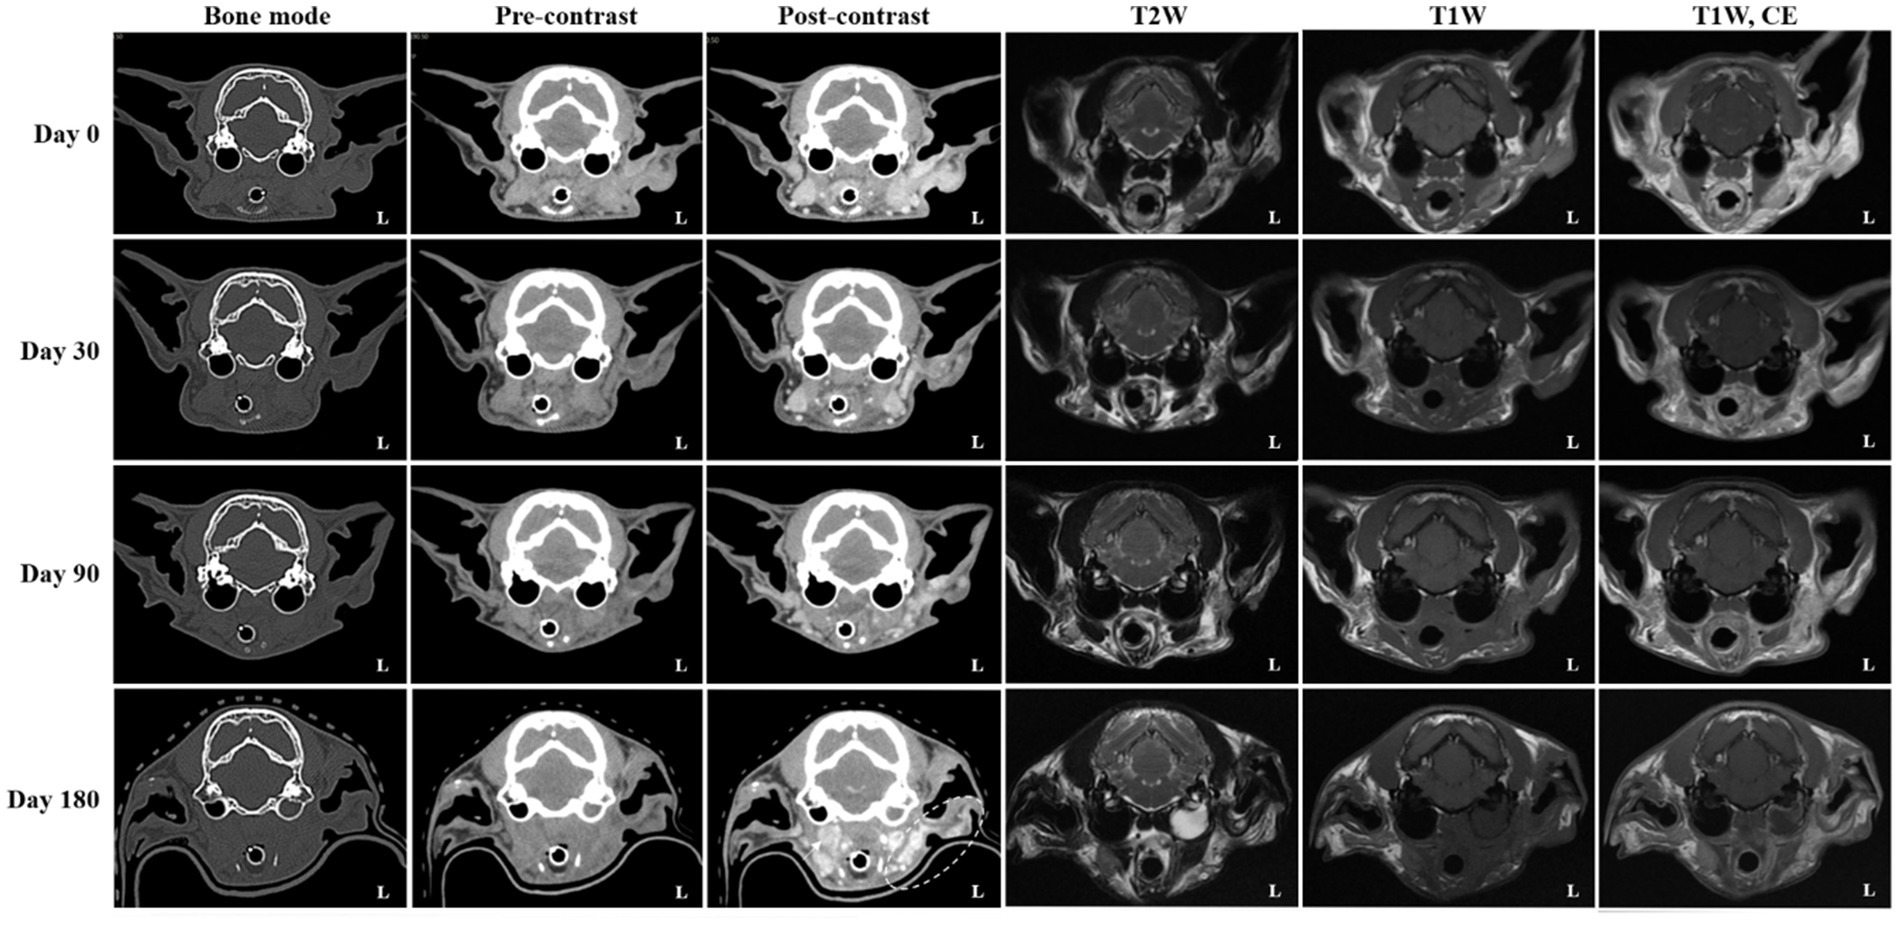

On day 0 (radiotherapy completion), cross-sectional imaging demonstrated a significant reduction in the size of the mass in the left external ear canal (Figure 3). However, residual soft tissue remained within the external auditory canal, and although the previously invasive component extending into the left parotid and mandibular regions regressed markedly, it continued to exhibit strong contrast enhancement. The residual lesion displayed poorly defined margins and induced medial displacement and compression of the adjacent masseter muscle. Additionally, findings suggestive of concurrent otitis externa included thickening and calcification of the external ear canal wall, along with a small volume of luminal fluid. The left mandibular, medial retropharyngeal, and prescapular lymph nodes remained enlarged and rounded, although they were notably reduced in size compared to pre-treatment imaging. The right medial retropharyngeal lymph node remained mildly enlarged. MRI revealed hyperintense lesions on DWI and corresponding hypointense regions on ADC maps in the left mandibular and parotid regions, which visibly decreased in both extent and intensity (Figure 4). The mean ADC value and size of the mass were measured at 469 × 10−6 mm2/s and 9.97 × 7.69 mm, respectively. On day 30, further regression of the mass within the external auditory canal was noted on conventional CT and MRI.

Figure 3. Serial computed tomography (CT) and magnetic resonance imaging (MRI) monitoring after palliative radiotherapy. Transverse post-contrast CT images obtained on days 0 (radiotherapy completion), 30, 90, and 180 illustrate temporal changes in the primary ear canal tumor and adjacent structures. Compared with pretreatment (baseline) images, the tumor showed more than a 50% reduction in maximal diameter at day 0, fulfilling the criteria for partial response (PR). By day 30, an additional ~30% reduction from baseline (approximately 80% total decrease) was observed, consistent with a continued PR. At day 90, only a minor further reduction (~10%) relative to the nadir was seen, maintaining a partial response (PR). By day 180, the lesion had increased by approximately 20% from the nadir and was accompanied by marked enlargement of the regional lymph nodes (arrow; left prescapular node not shown), meeting the criteria for progressive disease (PD). Additionally, fluid accumulation within the left tympanic cavity was evident on both CT and MRI, consistent with otitis media. The left parotid and mandibular regions (dotted circle) demonstrated increased contrast enhancement, raising suspicion for tumor progression or recurrence.

Nevertheless, contrast enhancement and indistinct margins persisted in the left parotid and mandibular regions. The mandibular and retropharyngeal lymph nodes continued to show a reduction in size, with only mild enlargement remaining. However, the left prescapular lymph node was notably enlarged compared to the previous scan. On DWI and ADC imaging, the signal intensity and size of hyperintense lesions on DWI remained similar to those on day 0. The mean ADC value and size of the mass was calculated at 320 × 10−6 mm2/s and 11.03 × 6.41 mm, respectively. On day 90, no significant changes in the size, extent, or imaging characteristics of the residual lesion were observed compared to day 30. Severe enlargement of the left prescapular lymph node, along with the mandibular, medial, and lateral retropharyngeal lymph nodes, remained similar. On DWI and ADC imaging, hyperintense lesions on DWI also remained stable. The mean ADC value and size of the mass were recorded at 448 × 10−6 mm2/s and 11.13 × 10.17 mm, respectively. Persistent findings in the left parotid and mandibular regions suggested the presence of residual neoplastic tissue.

On day 180, although the size and extent of the residual mass on conventional CT and MRI showed no remarkable changes, there was marked disease progression, characterized by marked enlargement of multiple lymph nodes, including the left medial retropharyngeal, left prescapular, and right medial retropharyngeal nodes. Furthermore, contrast enhancement in the left parotid and mandibular regions increased, indicating potential tumor recurrence or progression. Concurrent left-sided otitis media was newly identified. The mean ADC value and size of the mass was measured at 384 × 10−6 mm2/s and 7.53 × 8.62 mm, respectively. Based on serial CT and MRI evaluations, the tumor response in this case was classified according to the Veterinary Cooperative Oncology Group (VCOG) response evaluation criteria for solid tumors in dogs (v1.0) (15), using the maximal diameter of the primary lesion as the measurement parameter. Compared with the pretreatment baseline, the tumor size at day 0 showed more than a 50% reduction, fulfilling the criteria for partial response (PR). By day 30, an additional 30% decrease relative to day 0 was observed, resulting in an overall reduction of approximately 80% compared with baseline, consistent with a continued PR. At day 90, the lesion showed minimal further reduction (~10%) compared with the nadir, maintaining a partial response (PR). By day 180, the lesion had increased by approximately 20% from the nadir, accompanied by marked enlargement of regional lymph nodes, meeting the criteria for progressive disease (PD).